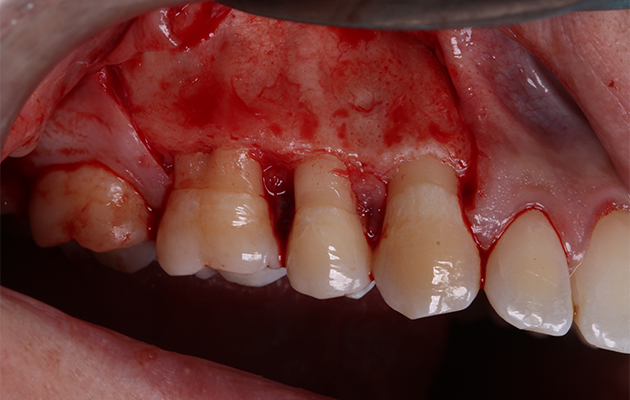

5 | Condição clínica pré-cirúrgica.

6 e 7 | Descolamento vestibular e janela de acesso à lesão.